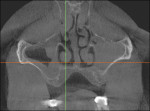

One of the most significant incidental pathological findings that may be seen in a CBCT scan of the maxillofacial region or the mandible is the extracranial carotid artery calcifications resulting from atheromatosis (Figure 5). Their most common location is the carotid bifurcation, where the common carotid artery splits into the external and internal carotid arteries. This occurs at the level of C3 and C4 vertebral bodies, posterior-laterally to the airway, an anatomical region that is included in FOV of the CBCT scan. Carotid atheromatosis is a silent disease that is associated with a high risk of stroke in older individuals and if identified by means of presence of calcifications in the respective blood vessels, the patient and the patient’s physician need to be informed for further investigation because CBCT is not the appropriate diagnostic tool to quantify the associated vascular obstruction. A detailed listing of the various incidental findings and their prevalence is seen in Table 1 and Table 2.